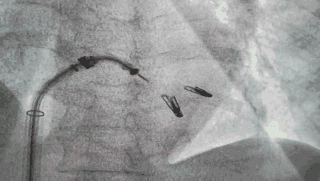

术中,导管经股静脉置入,经穿刺房间隔,进入左心房,到达二尖瓣目标位置。随后,在食道超声及X线引导下,王建安教授使用两个二尖瓣夹,准确捕获并夹合前、后瓣返流严重部位,使二尖瓣在收缩期由大的单孔变成小的双孔,从而减少二尖瓣返流。

术中释放二尖瓣夹